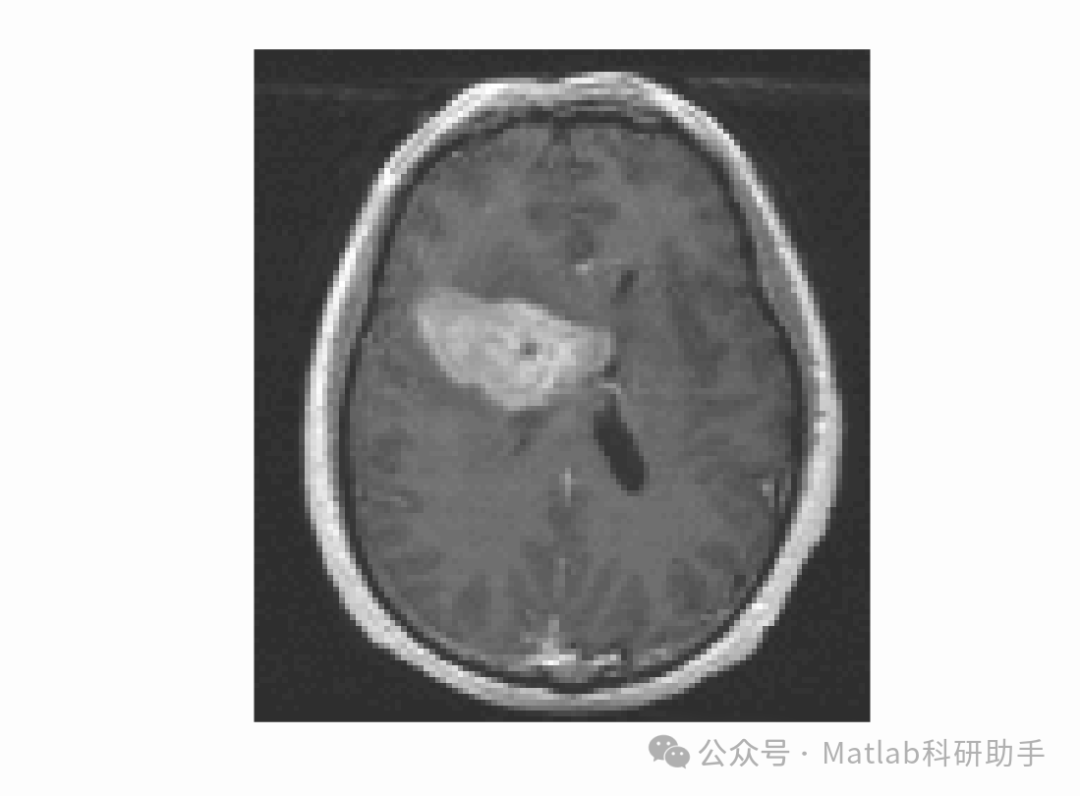

- 医学图像分割:

在CT、MRI等医学影像中,器官和病灶区域的灰度分布往往不均匀,该模型能够更准确地分割出目标区域,辅助医生进行诊断和治疗。